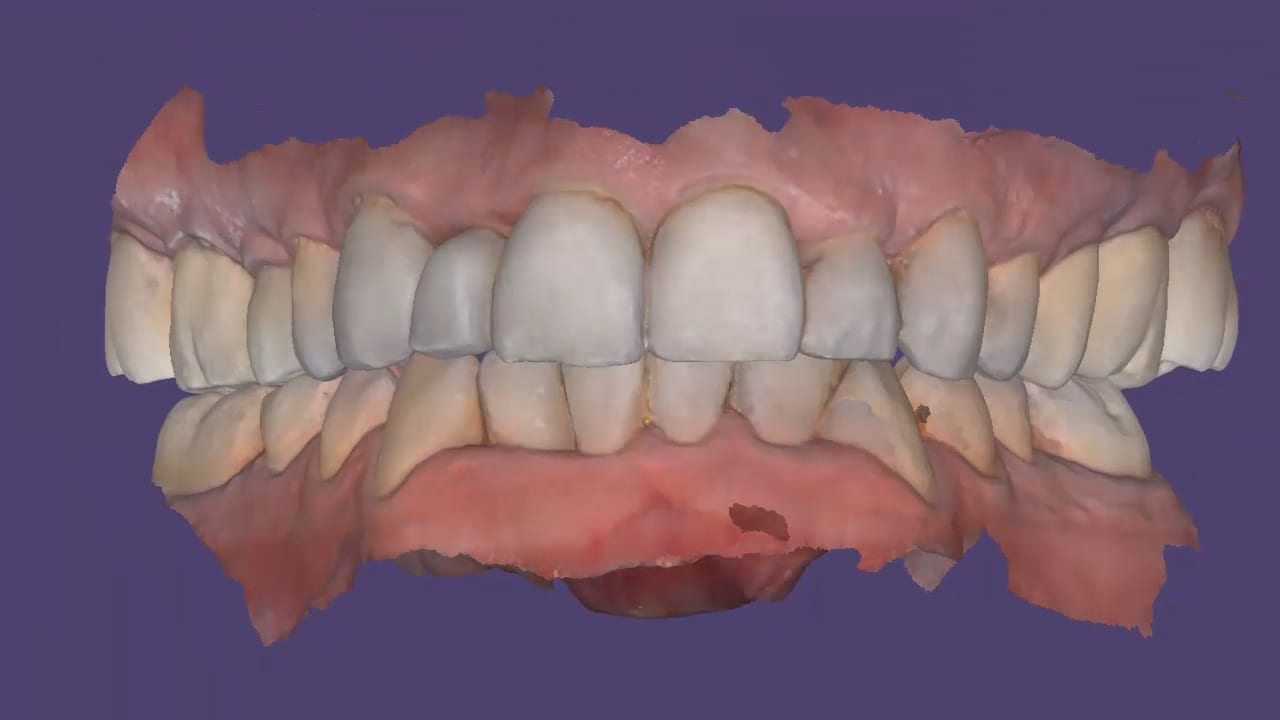

Post op intra-oral scan with Medit i500 to capture irritated and hemorrhaging tissue (for demonstration purposes only)